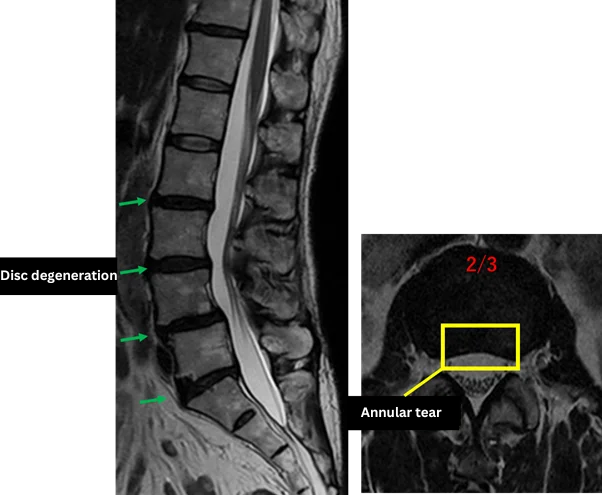

L1/2: No abnormalities

L2/3: Degeneration, annular tear

L3/4: Degeneration, disc bulging

L4/5: Degeneration, disc bulging, endplate degeneration (Modic type 2)

L5/S: Degeneration, disc bulging, endplate degeneration (Modic type 3)

The above findings were also observed on the imaging.

These findings indicate disc degeneration, disc bulging, annular tear, and endplate degeneration at L2/3, L3/4, L4/5, and L5/S, which are considered highly likely to be the cause of the primary symptoms.